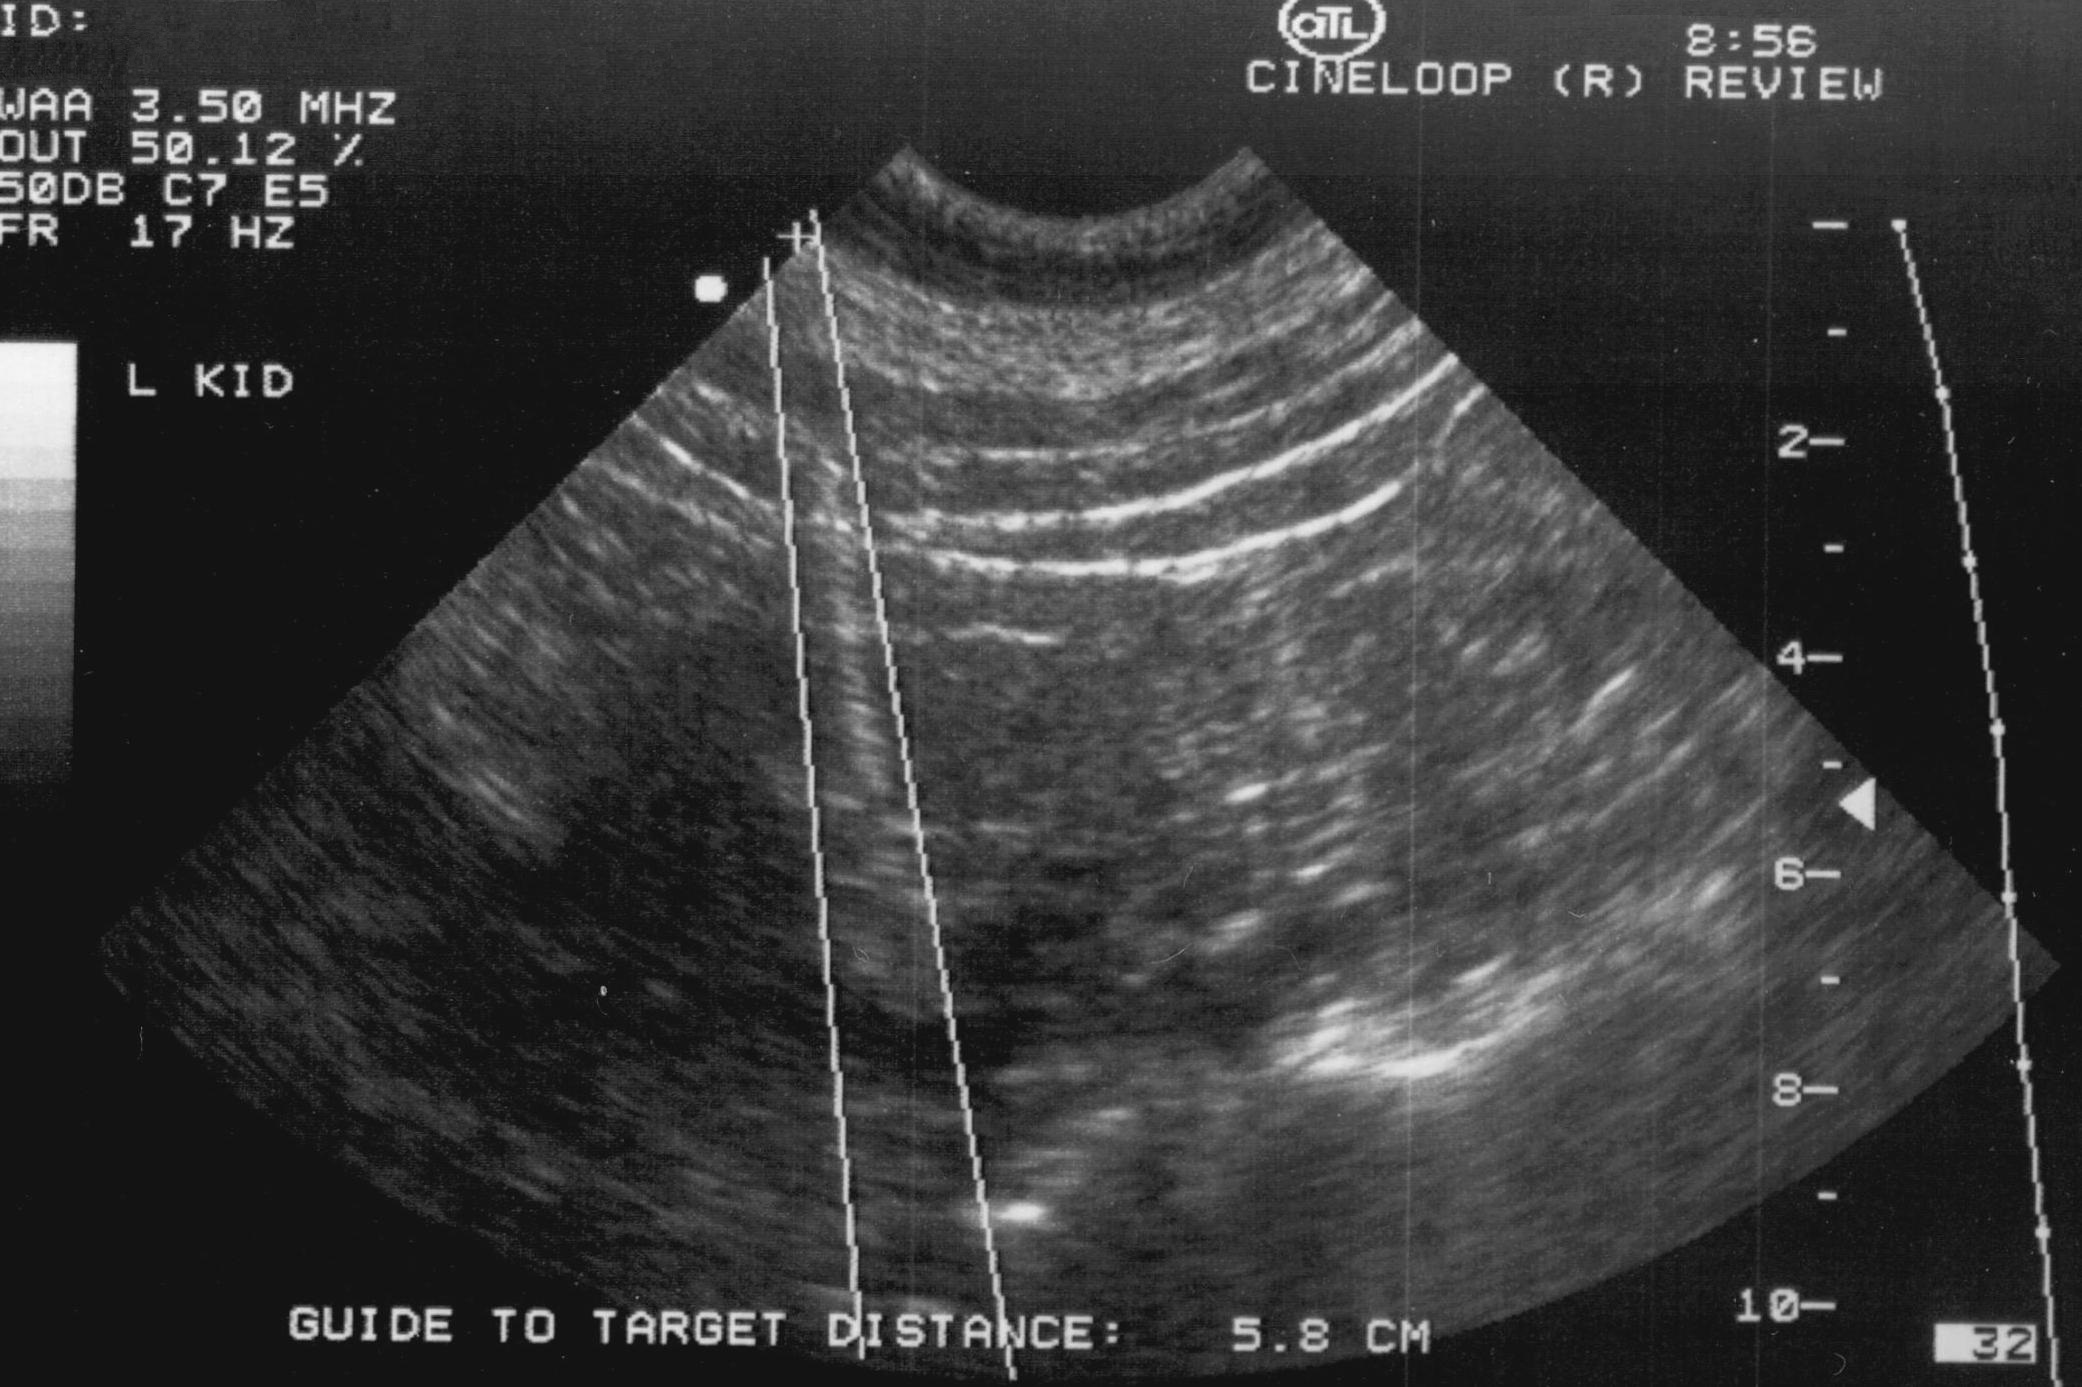

19.8. Urinary tract interventions

The most commonly performed intervention is US guided percutaneous nephrostomy. In special cases (obesity, visualization difficulties with US) CT guidance can also be chosen to create percutaneous nephrostomy. (Figure 30.)

Image

Figure 30. – Percutaneous nephrostomy contrast X-ray examination (CT guided catheter insertion)